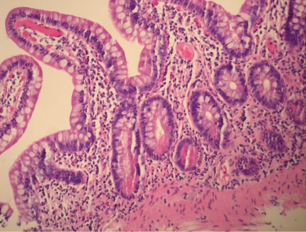

Πράσινο βέλος – εστιακή εξέλκωση κολικού βλεννογόνου. Κίτρινο βέλος – οίδημα και λεμφοκυτταρική διήθηση υποβλεννογόνιου χιτώνα (Ευγενική παραχώρηση Dr. V. Penopoulos)